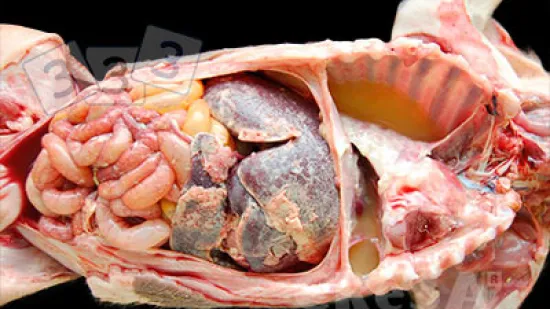

Semaine du 03-Mai-2021

Sur cette photo, on observe une atrophie thymique sévère sur un porcelet; de fait il y a un reliquat dans la zone péricardiaque, autour de la cavité thoracique. Lequel de ces agents infectieux peut avoir provoqué cette lésion ?